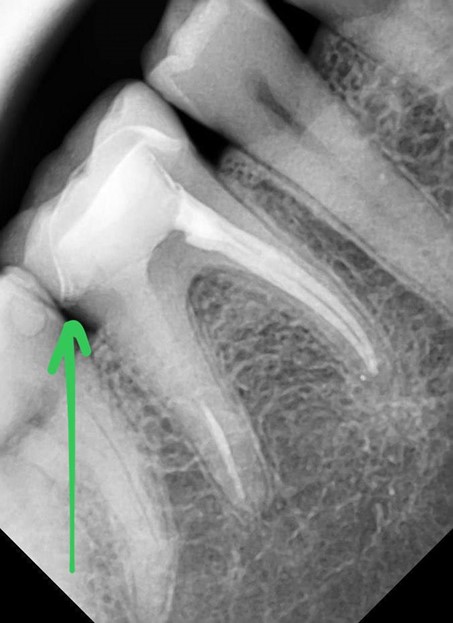

Нарушение герметичности коронки, поставившее под вопрос сохранность зуба

Самый частый случай подходов — разгерметизация коронки, вероятность около 4–5% на 16 зубов. Коронка может быть повреждена в результате какого-то механического нефизиологического воздействия (например, пациент получил по зубам хоккейной клюшкой, открыл пиво зубами, перекусил кабель на спор и так далее — всё это было), либо из-за нарушения адгезии. Проще говоря, через 3 года полимерный клей, на котором держится коронка, может деградировать. Не должен, но в ряде случаев может. Ещё в самой керамике могут быть внутренние напряжения из-за нагрузок и температурных градиентов, которые годы спустя выльются в то, что кусочек отколется. Обычные зубы стачиваются, если их годами сжимать и скрипеть ими ночью, а керамические коронки накапливают напряжение.

Если коронка разгерметизировалась недавно, лечение очень простое. Мы её снимаем, обеззараживаем очаг инфекции и возвращаем всё обратно в исходное состояние. Очень быстро, никаких рисков, никаких проблем, дёшево.

Заметили вовремя

Заменили коронку

Если коронка разгерметизировалась больше 4 месяцев назад, там будет обширный очаг разрушения. Грозит это чем угодно вплоть до нескольких операций. Но даже в простом случае это обширное вмешательство и долгие дорогие инвазивные работы.

Если мы даём гарантию, мы бы хотели видеть проблемные случаи сразу, а не спустя год, поэтому это работает так. Нарушение адгезии (напомню, крайне маловероятное) возможно с 1 по 4-й год, на пятый уже маловероятно, поэтому, да, такой срок.